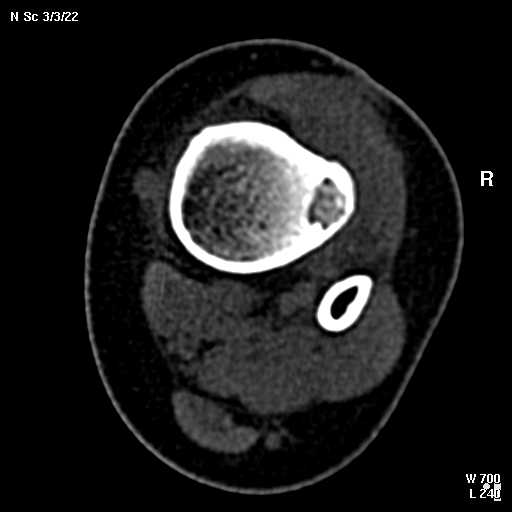

В обсуждении темы возникла необходимость дополнительных данных.

КТ изображения передаю на мой взгляд самые демонстративные. Их любезно записал коллега,

проводивший исследование в другом городе.

Прошу прощения за немного некоректную отправку КТ-снимков но по другому не получается :)